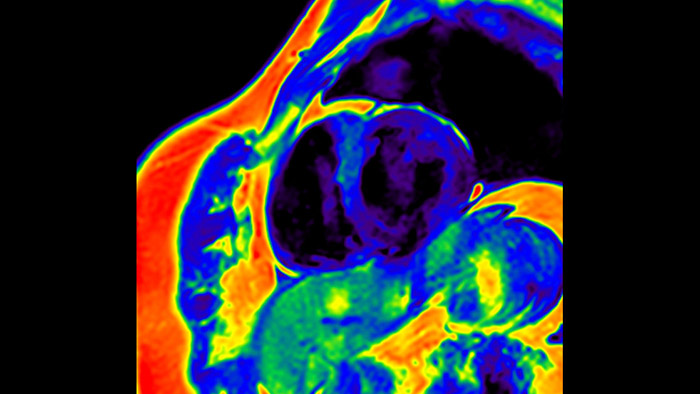

Diagnostic and prognostic utility of cardiac MR is increasing. Assess the anatomy and function of the heart using cine acquisitions, acquire information about perfusion and viability of the cardiac tissue, visualise potential edema with black blood sequence, access and even quantify tissue characterisation with CardiacQuant.

IntelliSpace Portal offers a Comprehensive Cardiac MRI Suite, providing dedicated workflows for functional analysis, viability, LGE, cardiac mapping assessment and RV/LV functional analysis in less than 5 min. per case1.